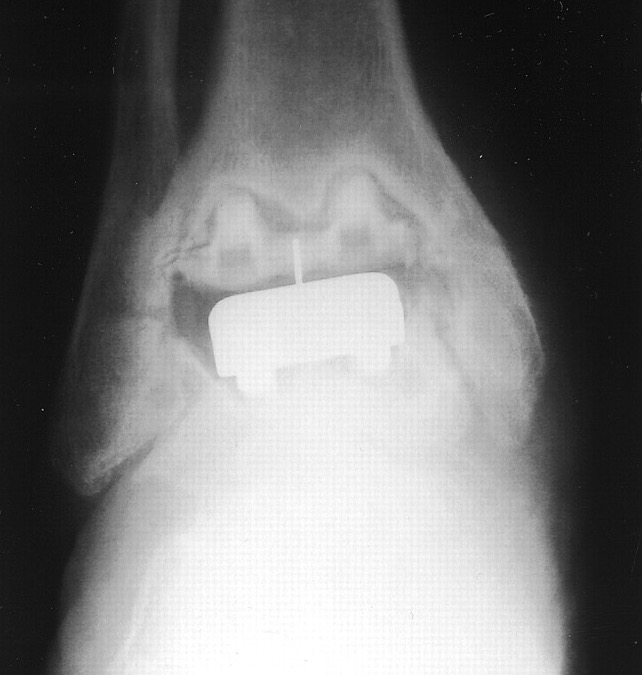

Loosening

Options

Athrodesis

Revision TAR

2 stage revision chronic infection

Arthrodesis

Revision

Results

Gross et al Foot Ankle Spec 2015

- systematic review of arthrodesis for failed TAR

- 80% union rate